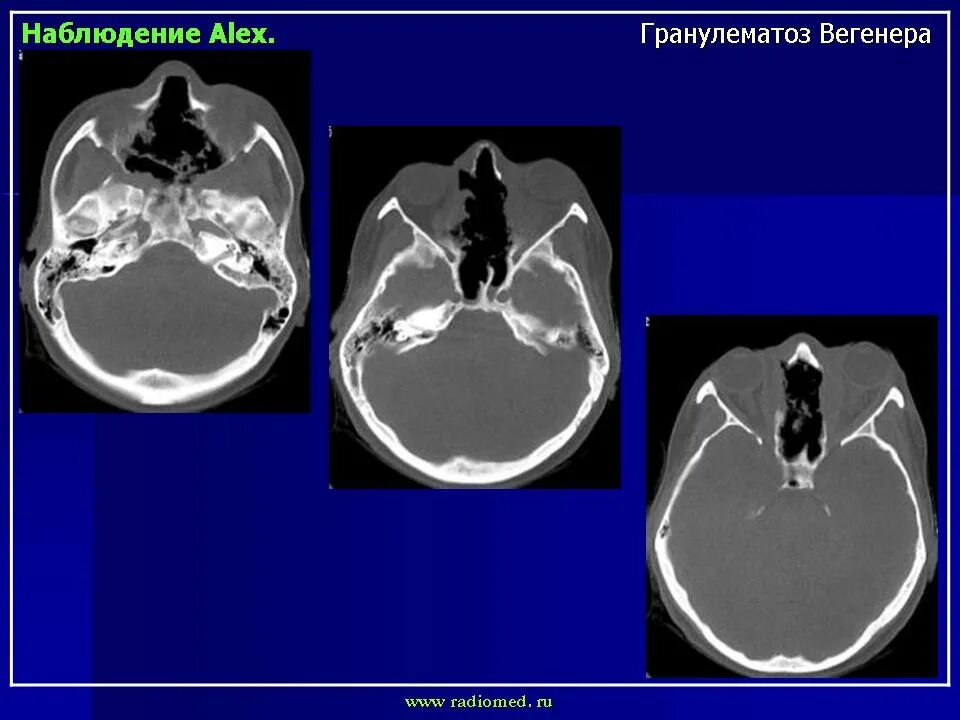

Гранулематоз лечение